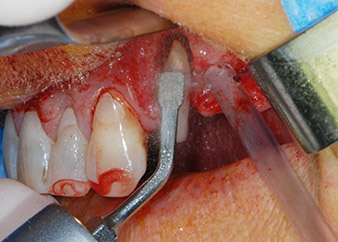

Zunächst wurde in einem Versuch, das Paro-Endo-Problem zu lösen, an der verbleibenden Wurzeloberfläche ein vorsichtiges Debridement mit einem piezochirurgischen Gerät vorgenommen (Piezomed, W&H) (Abb. 4); dann wurde der Apex mit dem gleichen Instrument im Sinne einer WSR abgetragen, um das verbleibende infizierte apikale Gewebe zu entfernen (Abb. 5). Eine retrograde Füllung war nicht notwendig, da die orthograde Füllung gerade revidiert worden war.

Brückenpfeiler

Abb. 4: Um den Zahn 24 als vorläufigen Brückenpfeiler zu erhalten, wird das Parodont mit einem piezochirurgischen Sytem gereinigt ...

bukkale Wurzelspitze

Abb. 5 ... und die bukkale Wurzelspitze mit dem gleichen Instrument abgetragen (WSR).